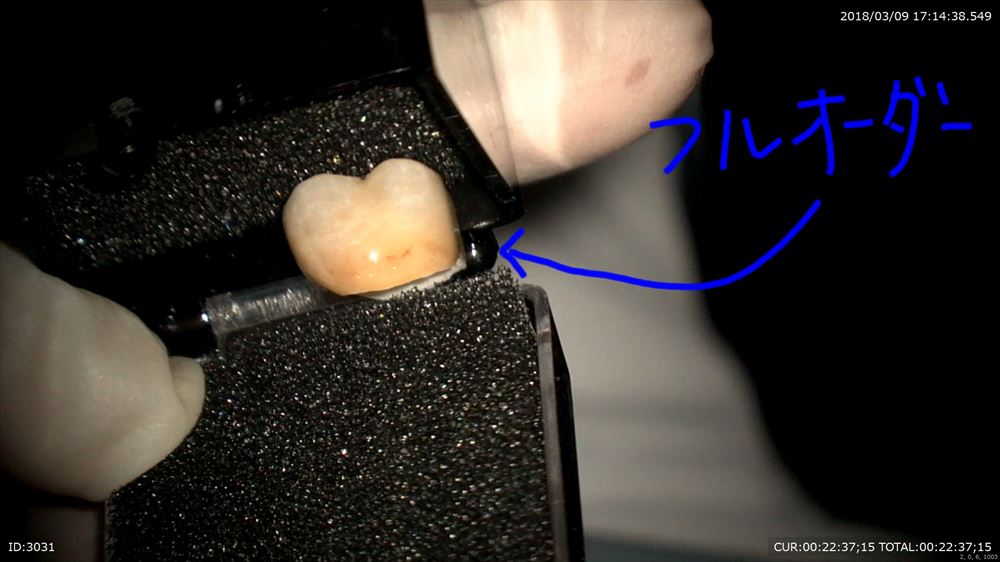

フルオーダーメイド

茶色の感じも今のお口を模倣しています。